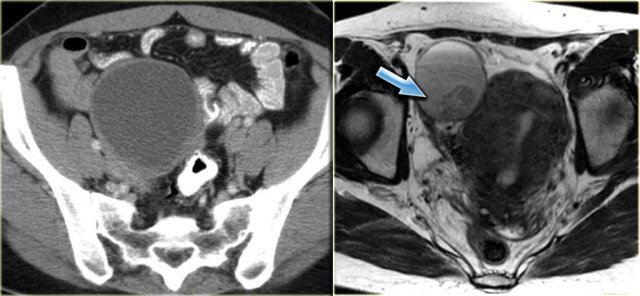

Ultrasound shows a complex solid-cystic mass in the left ovary, and another, very large complex solid-cystic mass in the right hemi-pelvis.

CT of the same patient shows a complex solid-cystic mass with thick, enhancing septations in the right ovary.

These findings are very suspicious for a malignant cystic neoplams.

There is also bilateral lymphadenopathy (arrows).

Pathology showed a serous ovarian cystadenocarcinoma.

This is the most common type of ovarian cancer.

On ultrasound both ovaries are markedly enlarged and contain cystic components with intracystic solid components (arrows).

The complex solid-cystic lesions, in addition to being bilateral, are suspicious for a cystic ovarian neoplasm and warrant further evaluation.

CT of the same patient confirms large bilateral complex solid-cystic lesions, bulging into the abdomen.